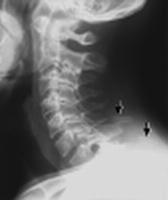

| Odontoid | #'s, dens-anterior arch distance (adults: < 3 mm; peds: < 5 mm) |

| Lines | Anterior spinal line, posterior spinal line, spinolaminar line, clivus base line |

| Lordosis | |

| Soft tissue swelling | Retropharyngeal, retroesophageal |